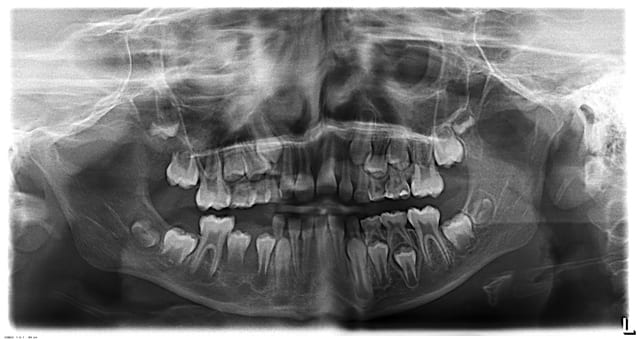

abcès important en regard de la 84, j'extrais ce jour la dent,mais comme je n'ai pas pu avoir une bonne rétro,je fais une pano,

est-ce qu'il y a une image au niveau de la 46 ?

problème au niveau de l'apex de 45 ?

en gros l'abcès (évolution en cellulite) peut-il être du à un problème sur 44 , 45 ou 46 ?

je pense vraiment que les lésions à l'apex de 44, 45 et 46 sont juste l'image de la formation des apexs et que cela n'a rien à voir avec une image infectieuse. Surtout, d'où serait venu les bactéries?

La 45 est bizarre, on dirait que la racine n'a quasiment pas été formée alors qu'elle n'est pas si profonde.

La radioclarté autour de 45 est douteuse.

Franchement, je ne vois pas en quoi 44 45 46 pourraient être mises en causes et l'apparence de radioclarté me semble plus liée à une ligne dense continue qui se prolonge en région symphysaire et qui s'apparente à un artéfact cinétique de la pano.

Ce serait quand même surprenant que sur les 2 panos il y ait eu un artéfact exactement au même endroit, et à l'endroit où on suspecte quelque chose.

il semble que l'absence de formation radiculaire de la 45 peut être due à la perte précoce de la 85

par contre il n'y a qu'une seule pano, j'ai juste agrandi pour que vous puissiez mieux y voir